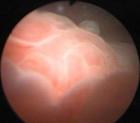

1.膀胱鏡可明確癌腫的位置數目及大小,常表現為團塊狀、潰瘍型菜花狀或廣基乳頭狀,表面不光滑,可有出血壞死周圍有充血水腫等炎症表現。伴有結石時可見結石區膀胱壁片狀隆起或潰瘍。